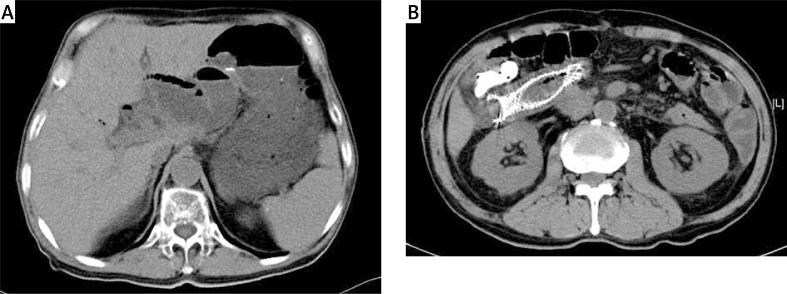

We analyzed 3 patients with malignant ALS after PD. They were treated by endoscopic enteral metal stent placement in our hospital. Meanwhile we retrospectively reviewed 49 cases with ALS after PD through available English literature. All these patients' clinical features, laboratory study, treatment and outcome were evaluated.

A total of 52 cases were analyzed in the study. The most common presenting symptoms of ALS after PD were jaundice (56.5%), upper abdominal pain (45.7%), fever (26.1%), and vomiting (23.9%). Sixty percent of ALS cases were caused by tumor recurrence. The mean time from prior surgery to diagnosis of ALS was 13.3 months. The rates of treatment with the endoscopic approach, percutaneous stenting or drainage, surgery, and the conservative method were 40.4%, 32.7%, 11.5%, and 15.4%, respectively. Endoscopic enteral metal stent placement proved more effective and less invasive in the treatment of malignant ALS after PD.

Cholangitis and cholangiectasis are the major manifestations of malignant ALS after PD. Invasive interventions are enjoying more and more acceptance for treatment. Endoscopic enteral metal stent placement appears to be a promising technique with effective palliation in these patients.

我们分析了3例PD术后发生恶性ALS的患者。在我院,他们接受了内镜下肠道金属支架置入术治疗。同时,我们通过现有英文文献对49例PD术后ALS患者进行了回顾性分析。对所有这些患者的临床特征、实验室检查、治疗及预后进行了评估。

本研究共分析了52例患者。PD术后ALS最常见的症状为黄疸(56.5%)、上腹部疼痛(45.7%)、发热(26.1%)及呕吐(23.9%)。60%的ALS病例由肿瘤复发引起。从上次手术至诊断为ALS的平均时间为13.3个月。内镜治疗、经皮支架置入或引流、手术及保守治疗的比例分别为40.4%、32.7%、11.5%和15.4%。内镜下肠道金属支架置入术在治疗PD术后恶性ALS方面被证明更有效且侵入性更小。

胆管炎和胆管扩张是PD术后恶性ALS的主要表现。侵入性干预在治疗中越来越被接受。内镜下肠道金属支架置入术似乎是一种有前景的技术,能有效缓解这些患者的症状。